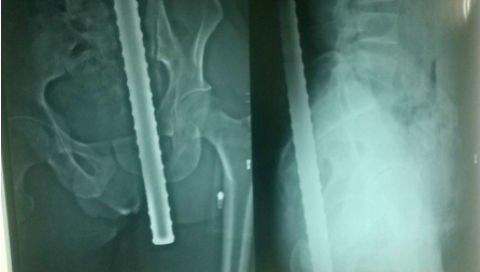

Nối bàn chân đứt lìa cho người đàn ông 38 tuổi gặp tai nạn máy cắt cỏ

Khi đang cắt cỏ, anh L.V.T (38 tuổi, Văn Chấn, Yên Bái) bất ngờ bị lưỡi của máy cắt cỏ làm đứt rời hoàn toàn bàn chân trái. 6 tiếng sau tai nạn, bệnh nhân được chuyển cấp cứu tới Bệnh viện Hữu nghị Việt Đức.